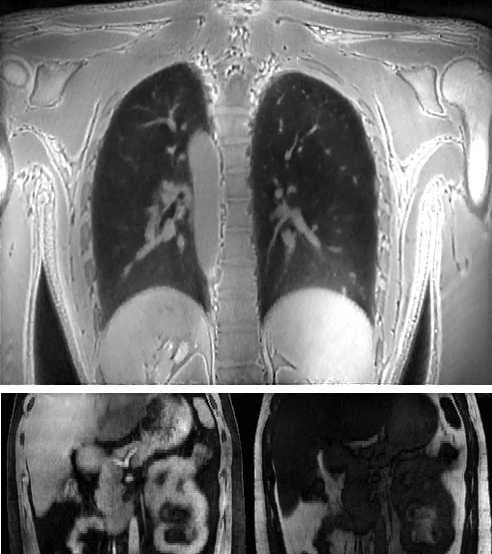

Medical imaging is now used extensively for accurate diagnosis, real-time intervention, and precision medicine. Our work has been focused on fast, high-resolution imaging augmented with functional and metabolic mapping. For example, dynamic 4D MRI under free breathing has been developed using PNCRNNs, with the reconstruction time as fast as 50 bin per second, offering substantial improvement of the image quality for dynamic golden-angle radial imaging of the abdomen. Novel imaging techniques have been developed for high-resolution whole-brain neurometabolic mapping, shedding light on in vivo molecular biomarkers for various brain diseases including stroke, brain tumor, and neurodegenerative disorders. A model-based deep learning architecture, referred to as MoDL-QSM, was developed with improved accuracy for quantifying tissue susceptibility for precise electrode implantation for deep-brain stimulation. To meet the demands for automated identification and localization of the vertebrae, pancreas, colon, lung nodules and other organs in low-dose CT, algorithms integrating local image details and global image patterns have been proposed. To extend the clinical use of nonlinear regression in medical imaging and image analysis, a deep negative correlation learning framework has been proposed to yield a deep regression of ensemble where each base model is both accurate and generalisable.

Dynamic 4D MRI of the abdomen

Vertebrae identification and localization